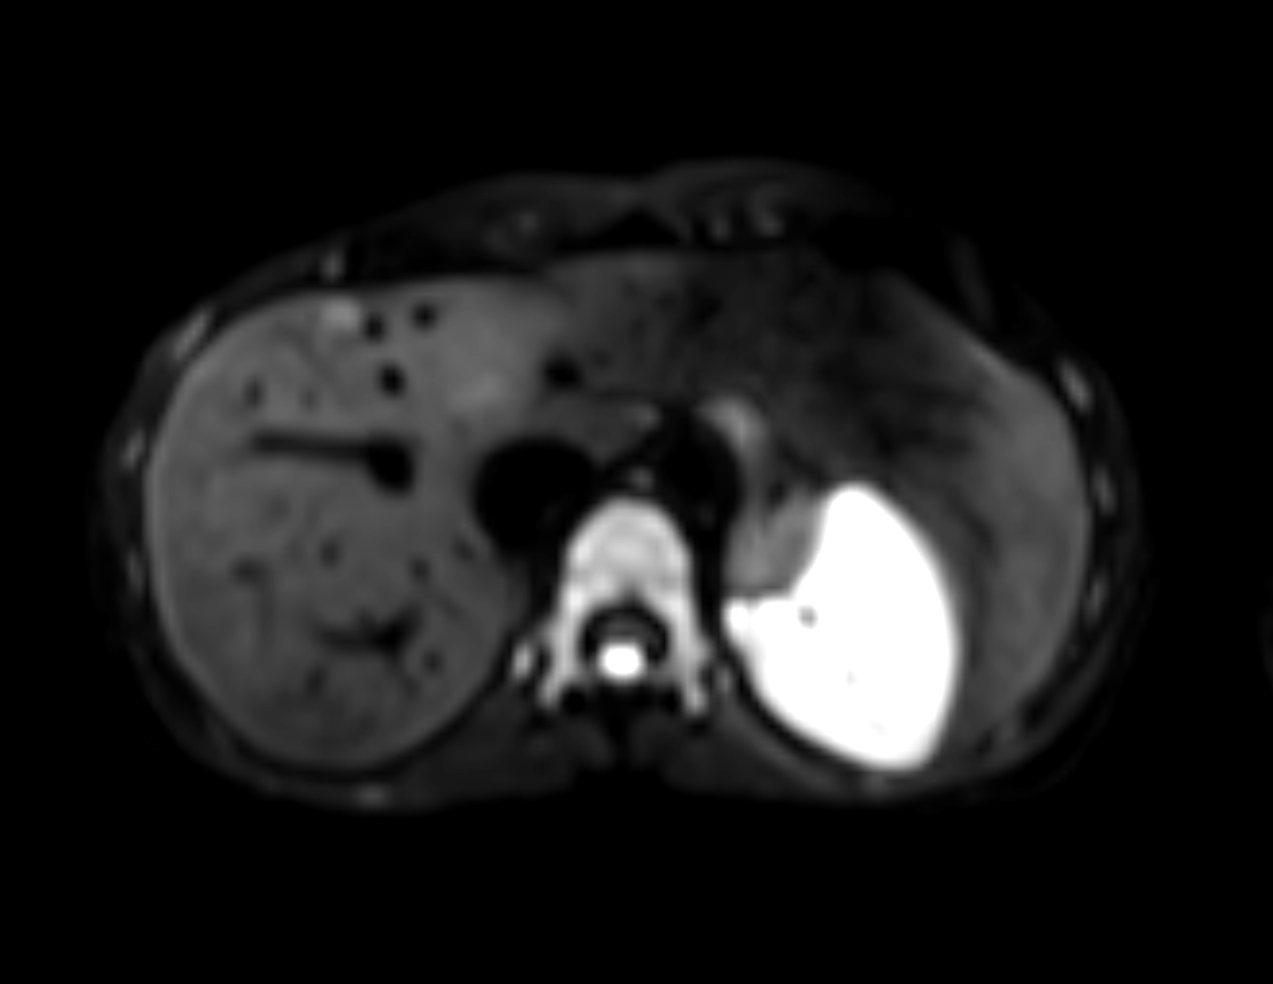

Axial DWI (ADC)